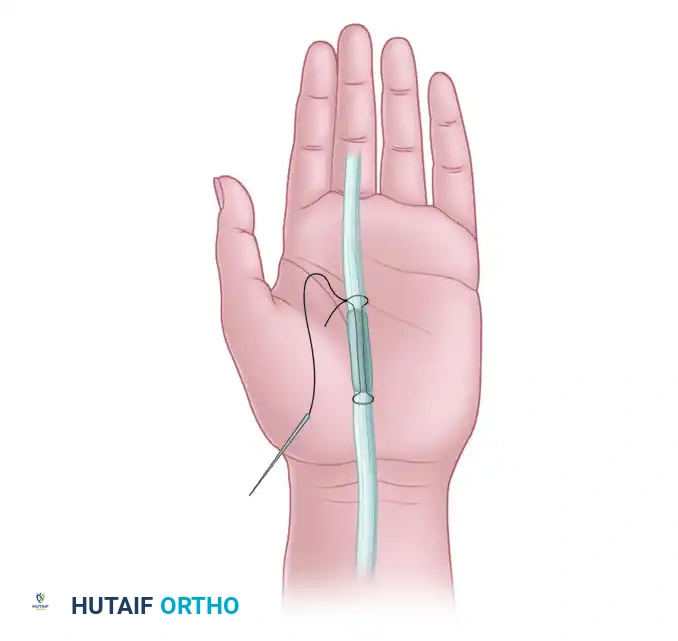

Step 3: Suture Placement

Place a heavy, non-absorbable core suture (e.g., 3-0 or 4-0 Prolene) into the proximal stump of the FDP using a modified Kessler or Bunnell configuration. Ensure the suture grasps the tendon securely.

Figure 2: Placement of a locking core suture through the proximal stump of the flexor digitorum profundus tendon.